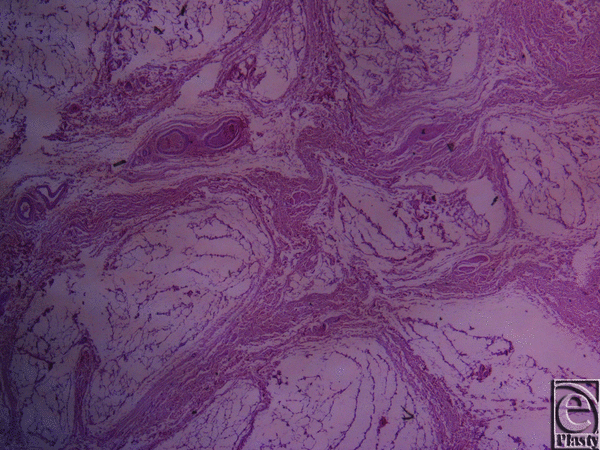

Microscopic evaluation of skin specimens revealed normal dermis and appendages in all cases. In all sections of the inframammary crease specimens, no breast parenchyma was present. In the subcutaneous tissue, there was a well-defined network of dense collagen fibers that create a beehive pattern of the subcutaneous fat (Fig 3). This pattern is denser in the deeper sites in relation to the fascia of the underlying muscle (Figs 4, 5a, and 5b). The collagen fibers network has a broad base of attachment to the dermis. In the sections from the medial sites of the crease, the beehive pattern has the same structure as that described earlier but appears looser. However, it becomes denser in the deeper sites. In the sections of the lateral sites of the crease, the beehive pattern is equally well organized, with broad base attachments of the collagen bundles to the dermis (Fig 6). In some of the cases, the bundles are thinner than those at the other sites. The elastic fibers participate in the formation of the collagen pattern and radiate in a relatively parallel pattern in the reticular dermis and in a perpendicular fashion in the papillary dermis (Fig 7).

![]() |

| Figure 7. Inframammary crease. Orsein stain ×25. The elastic fibers have a parallel pattern in the reticular dermis and a perpendicular pattern in the papillary dermis. |